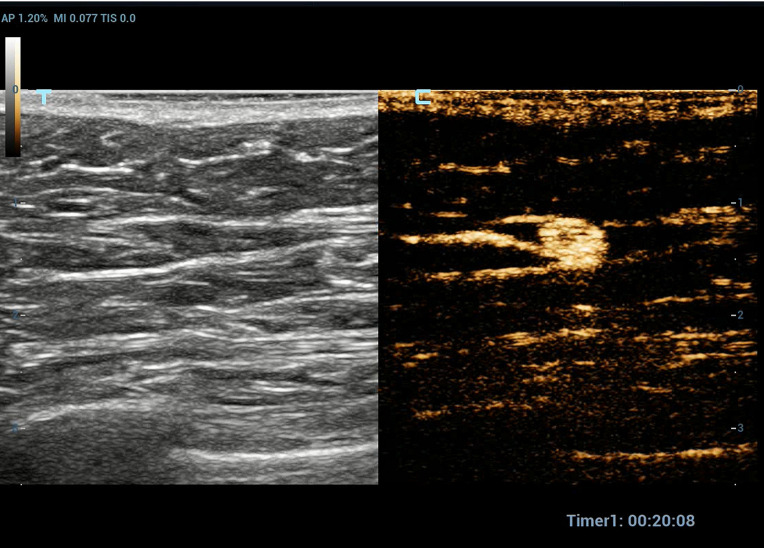

Methods: A total of 176 patients with breast cancer who underwent preoperative SLN-CEUS to trace axillary sentinel lymph nodes were included. The positive result of SLN-CEUS was defined as both lymphatic vessels and SLN visible. The negative result was defined as the visible lymphatic vessels but the SLNs invisible, and neither lymphatic vessel nor SLNs invisible. Clinical features, histopathology, ultrasound features and doses of contrast agents were analyzed between the positive and negative groups.

Abstract Image